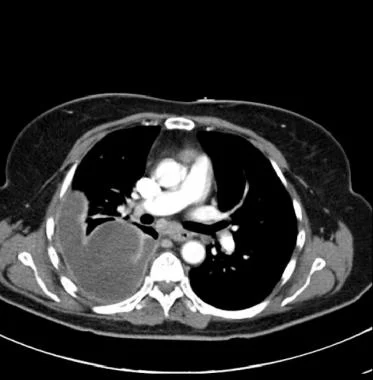

图4 吸入性肺炎导致米勒链球菌和厌氧菌的脓胸患者。对比增强CT显示胸膜增厚、胸腔积液密度高、分房和分隔。胸腔穿刺出现恶臭脓液。

胸膜增强可见于活动性炎症和严重胸膜肺感染的患者,可能是复杂性胸腔积液或脓胸的一个征象。胸部增强CT示胸膜分裂征,常见于脓胸,被积液分隔的双侧胸膜增强,如下图所示。